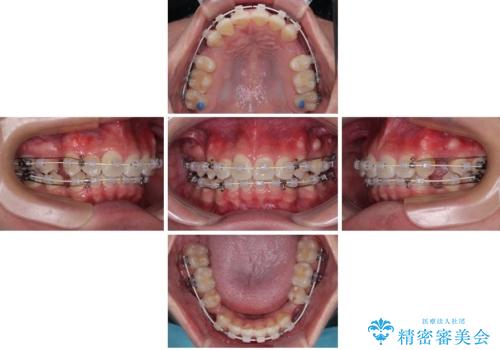

抜歯矯正で叢生と正中のずれを改善|審美装置による矯正症例

- 今回ご紹介するのは、

「全体的なデコボコ(叢生)」「上下の正中のずれ」 を主訴として来院された20代男性の患者様の症例です。

叢生が強く、歯が並ぶスペースが不足していたため、

上下左右の第一小臼歯を抜歯して、矯正治療のための適切なスペースを確保する計画としました。